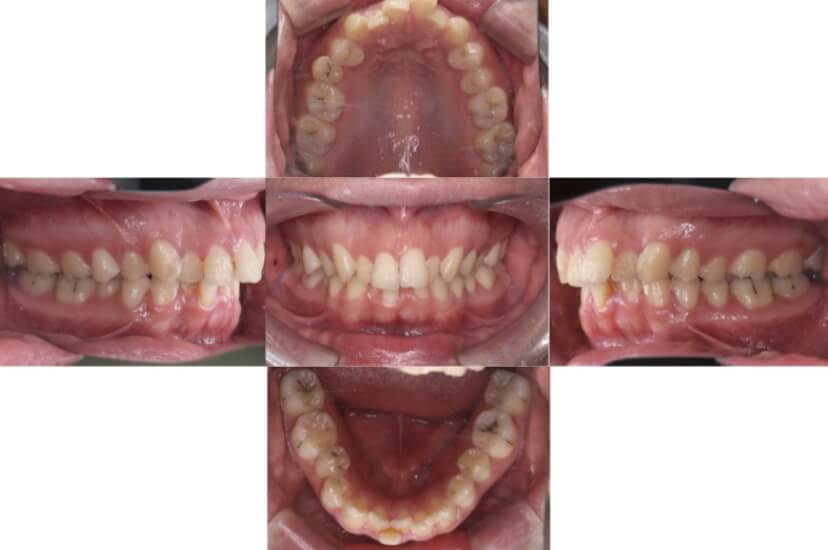

上下顎叢生(上下の前歯のガタガタ)のケースです。

装置はラビアル(上下表側)で、右上以外の小臼歯を3本、右上は犬歯の抜歯を行っています。抜歯したスペースを使って、上下の前歯の後方移動と叢生(ガタガタ)の改善を行っています。

主訴 八重歯を治したい。

年齢・性別 27歳 女性

お住まいの地域 東京都港区

治療方針 抜歯スペースを利用して上下前歯の叢生(ガタガタ)の改善

抜歯部位 上顎右側犬歯、上顎左側第一小臼歯、下顎両側第一小臼歯

使用装置 ラビアル(上下表側)、顎間ゴム

治療期間 3年3か月

治療回数 25回

BEFORE